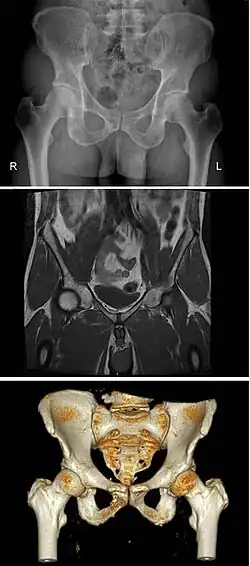

Additional images

Diameters of pelvic inlet